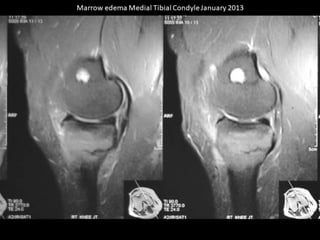

The document presents a detailed case study of a patient with transient osteoporosis of the hip (TOH) and spontaneous osteonecrosis of the knee (SONK) treated at Choithram Hospital & Research Centre in India. Over 20 years, the patient experienced multiple episodes of TOH and SONK with no history of trauma or co-morbidities, resulting in resolutions and recurrences of conditions. The information is intended for orthopedic surgery students and highlights personal experiences and case collections, with a disclaimer regarding content usage and potential controversies.